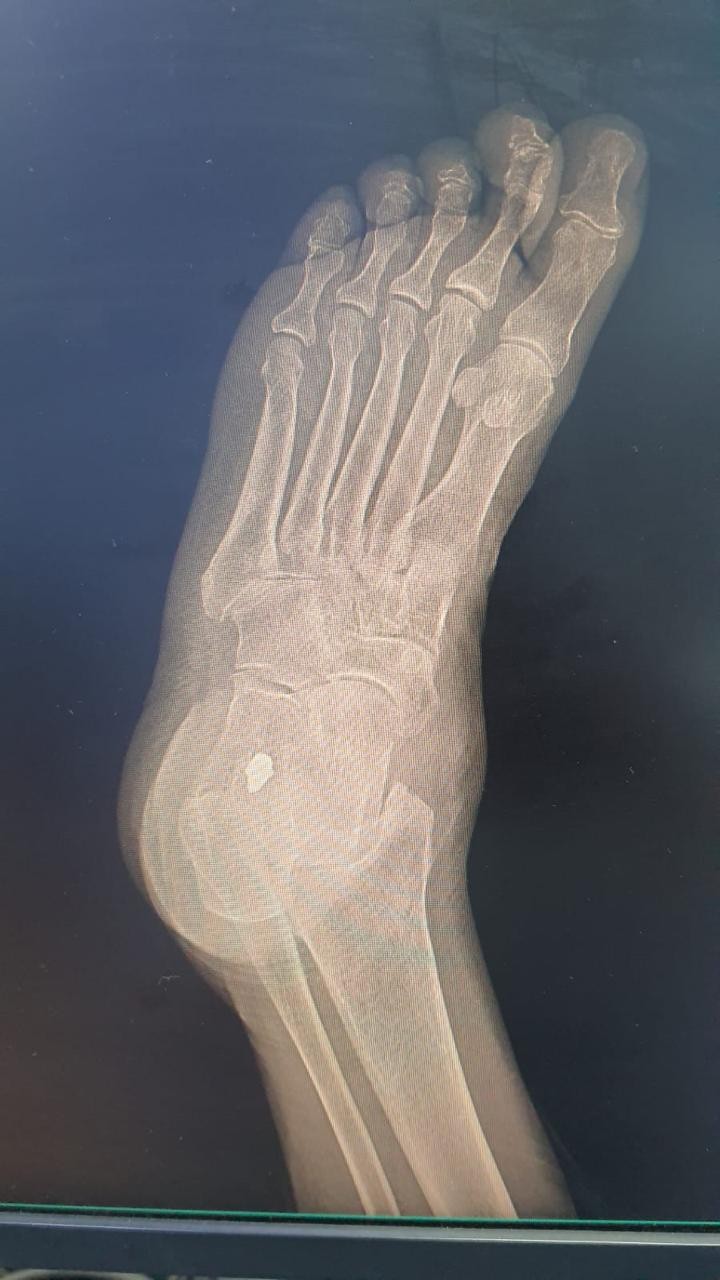

وفي التفاصيل أوضح التجمع أن الحاجة التي راجعت قسم الطوارئ بالمستشفى أثناء مرورها بمنطقة القصيم في رحلة العودة لبلدها بعد تأدية مناسك الحج وكانت تشكو من ألم متكرر منذ سنوات طويلة في كاحل القدم اليسرى مع وجود ورم في نفس المكان يزداد حجما مع المشي مما أثر على حركتها ونشاطها الطبيعي، مشيرا إلى أن الفحوصات والأشعة السينية التي أجريت للمريضة بالمستشفى أظهرت أن معاناتها ناجمة عن وجود شظية في مفصل الكاحل الأيسر.

ولفت إلى أن الفريق الطبي بإشراف الدكتور جلال هادي استشاري جراحة العظام قرر إجراء عملية جراحية للمريضة تم خلالها استخراج الشظية بمساعدة جهاز الأشعة مع المحافظة على سلامة الأوعية الدموية والأعصاب القريبة منها.